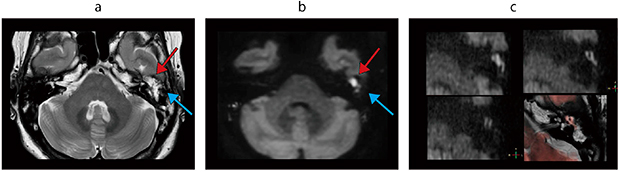

図2 Ingenia 3.0T CX(80mT/m)による高画質拡散強調画像

a:dS Zoom DTI,FOV:180mm

b:高SNR DWI,b=1000,211matrix,TE:89ms

c:dS Zoom T2Wとb800 DWI,FOV:200mm×140mm,slice thickness:3mm

(画像ご提供:静岡県立静岡がんセンター様)